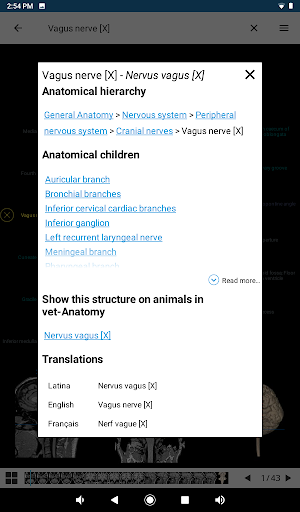

*Browse between anatomical parts using description links

-In the details view of an anatomical structure related terms are now displayed